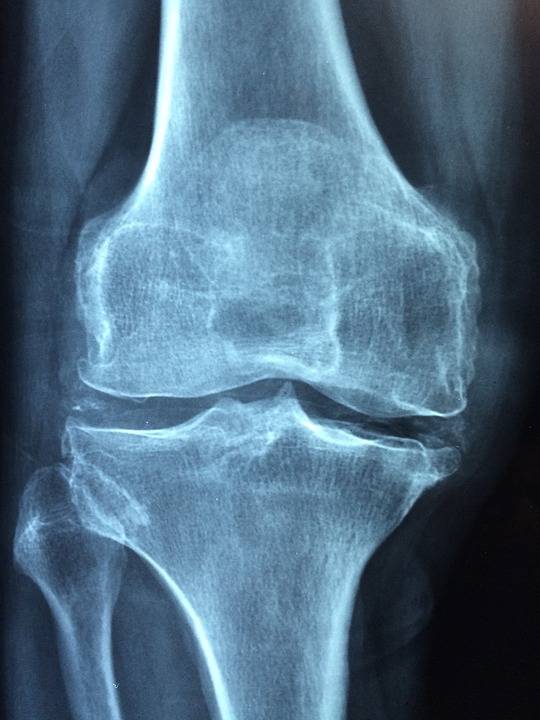

Est-ce que la cryothérapie corps entier peut soulager les douleurs articulaires d'une arthrose ?

L'arthrose est une maladie articulaire fréquente qui se caractérise par la dégénérescence progressive du cartilage. Le...